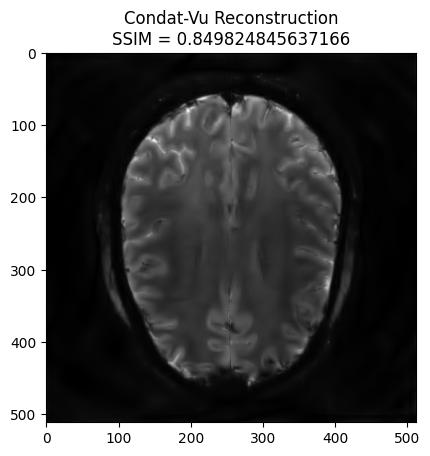

Analysis formulation: Condat-Vu reconstruction#

#linear_op = WaveletN(wavelet_name="sym8", nb_scales=4)

linear_op = WaveletUD2(

wavelet_id=24,

nb_scale=4,

)

regularizer_op = SparseThreshold(Identity(), 1e-9, thresh_type="soft")

# Setup Reconstructor

reconstructor = SelfCalibrationReconstructor(

fourier_op=fourier_op_sense,

linear_op=linear_op,

regularizer_op=regularizer_op,

gradient_formulation='analysis',

verbose=1,

WARNING: Making input data immutable.

Lipschitz constant is 11.98557472229004

x_final, costs, metrics = reconstructor.reconstruct(

kspace_data=kspace_obs,

optimization_alg='condatvu',

num_iterations=200,

image_rec = pysap.Image(data=np.abs(x_final))

plt.imshow(np.abs(image_rec), cmap='gray')

recon_ssim = ssim(image_rec, image)

plt.title('Condat-Vu Reconstruction\nSSIM = {}'.format(recon_ssim))

plt.show()

- mu: 1e-09

- lipschitz constant: 11.98557472229004

- tau: 0.15362178825549028

- sigma: 0.5

- rho: 1.0

- std: None

- 1/tau - sigma||L||^2 >= beta/2: True

- data: (512, 512)

- wavelet: <mri.operators.linear.wavelet.WaveletUD2 object at 0x7e8282e45090> - 4

- max iterations: 200

- number of reweights: 0

- primal variable shape: (512, 512)

- dual variable shape: (2621440,)

----------------------------------------

Starting optimization...

WARNING: <class 'mri.operators.linear.wavelet.WaveletUD2'> does not inherit an operator parent.

- final iteration number: 200

- final cost value: 1000000.0

- converged: False

Done.

Execution time: 707.4618570560051 seconds